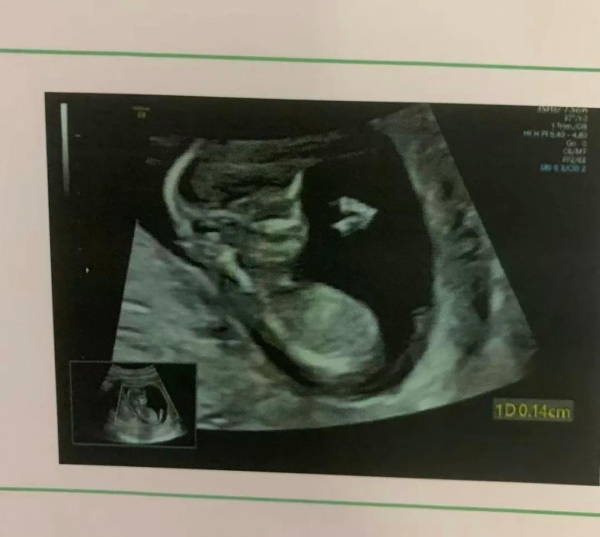

转折出现在八月。孕反终于好转,肚子也渐渐隆起。有一天去做四维B超,屏幕上出现了那个婴儿的小小身影--圆圆的脑袋、圆圆的肚子。医生笑着指给她看:"TA在动呢。"邓思蓉的眼泪瞬间涌了出来,"好可爱呀。"

邓思蓉在B超中看到孩子

那一刻,她的心被彻底融化,彻底接受了即将成为母亲的现实。